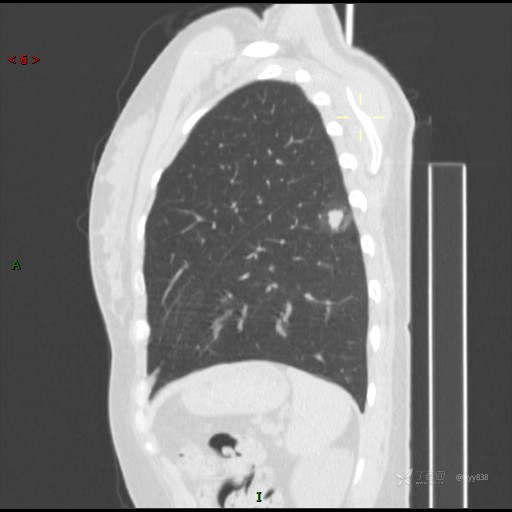

胸膜下“煎鸡蛋征”,感染 VS 炎症 VS 肿瘤,挑战有你---结果公布~

患者性别:女

患者年龄:46岁

简要病史:干咳半月伴左胸部不适

辅助检查:CT

临床诊断:结节

讨论:病变性质?